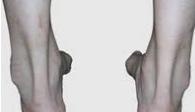

①下图的右方就是膝下O,指的是膝盖可以靠起来,但膝下弯弯的一个O.下图的左方这个女生是平时是股骨内旋的O型腿(内股O腿,"内旋大腿"),但用力并拢后是膝下O腿。

②膝下O腿的原因是,股骨内旋了,但胫骨比起它原来该有的位置外旋了,这是最难矫正的一种腿,也需要综合矫正,你的骨盆、你的股骨、小腿、脚踝需要整体矫正。

③膝下O腿的特征1)大腿内旋2)小腿相对外旋3)小腿外前侧肌肉紧张僵硬4)小腿的外上侧腓骨小头突出 5)膝上距离很近,但小腿以下距离相对就远很多,不是像内股o腿。6)膝盖整体来说扭曲很大,内股o腿的人是整体的膝盖向内转。

④膝下O腿(XO型腿)和大腿内旋型的O型腿的差别是,大腿内旋性O型腿大腿和小腿都是同步内旋的,所以矫正治疗相对简单。而XO型腿一般是大腿内旋,小腿相对外旋,所以矫正起来复杂。